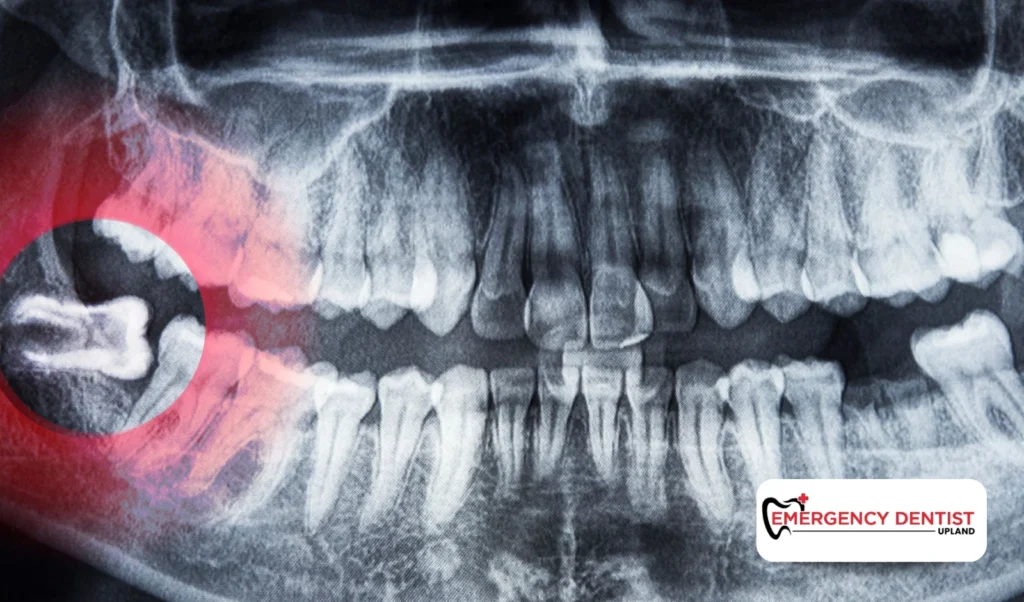

If you are wondering how to get accurate wisdom tooth removal cost, scheduling a dental evaluation is the best first step. X-rays allow the dentist to see tooth position and determine the appropriate extraction approach.

An impacted wisdom tooth does not fully break through the gums. This can lead to pressure, swelling, infection, or damage to surrounding teeth.

Because impacted teeth often require more planning and surgical steps, they commonly affect the average cost of a wisdom tooth removal more than straightforward extractions.